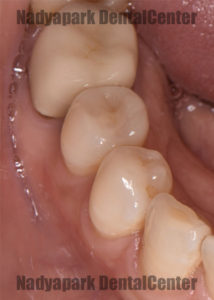

セラミック装着後のお口の中の写真です。

セラミックは保険外の治療ですが、保険の金属による治療と比べて以下のような利点があります。

・審美性に優れる

・金属アレルギーの心配がない

・歯との接着力が強い

・虫歯が再発しにくい

・経年変化が少ない

・再治療になるリスクが低い